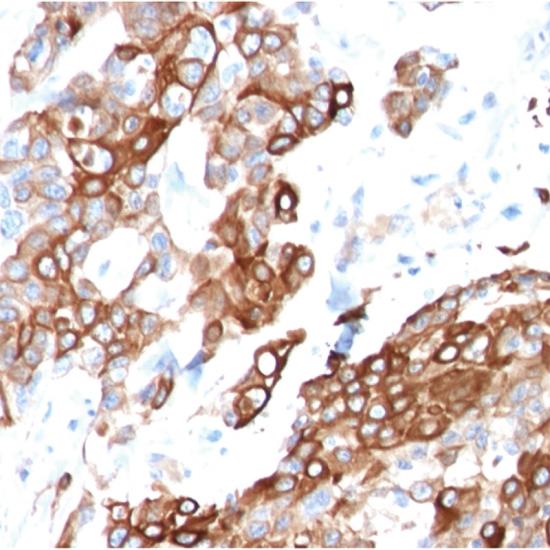

兔抗人神經(jīng)調(diào)節(jié)蛋白1(Nrg-1)多克隆抗體

• 預(yù)處理:

熱修復(fù)

• 陽性部位:

細(xì)胞漿

• 陽性對(duì)照:

乳腺癌

Nrg-1(神經(jīng)調(diào)節(jié)蛋白1),屬于表皮生長(zhǎng)因子家族的一員,是一類介導(dǎo)細(xì)胞間相互作用的信號(hào)蛋白,主要表達(dá)于腦、心臟、乳腺等組織中,參與組織細(xì)胞的發(fā)育和成熟。